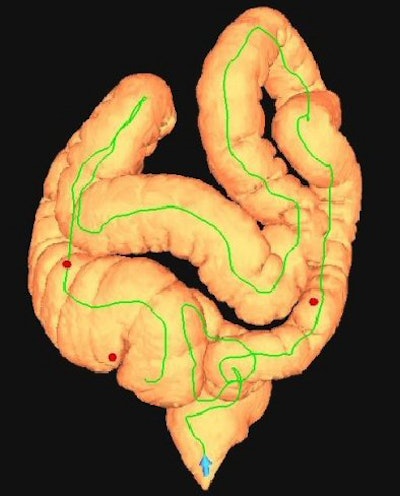

| Top, colon map from screening CTC shows the location of three polyps that measured 6-9 mm in size (C-RADS 3 classification). Below, 3D endoluminal CTC image shows a 6-mm polyp in the ascending colon. Bottom, image from same-day optical colonoscopy shows the same polyp, which proved to be a tubular adenoma. The other two polyps (8 and 9 mm in size) also proved to be tubular adenomas. All images courtesy of Dr. Perry Pickhardt. |